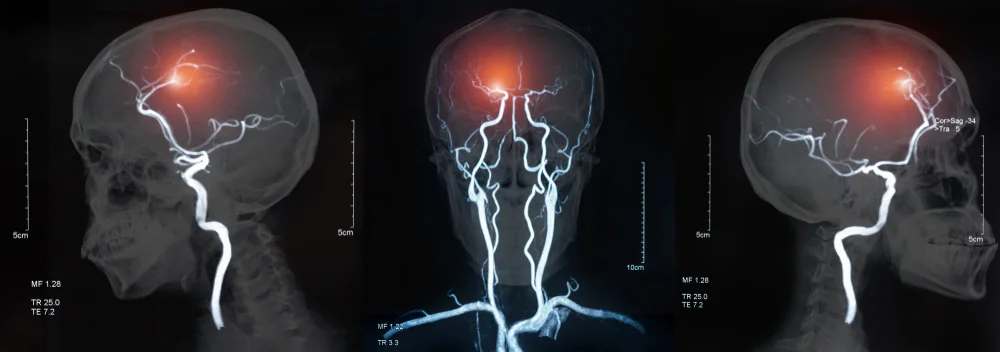

התוצאה: אבחנה שגויה, טיפול תרופתי שגוי - ואירוע מוחי קשה שבעקבותיו הפכה נאוה לנכה סיעודית.

לאורך השנים, מצבה של נאוה לא רק שלא השתפר - אלא הלך והחמיר. בסופו של דבר היא לקתה באירוע מוחי חריף, ואושפזה במצב קשה בבית החולים שיבא תל השומר. רק שם, לטענת עורכי דינה, נעשתה האבחנה הנכונה - והיא הוגדרה לראשונה כחולה ב-APLA.

היום, לפי המסמכים שהוגשו לבית המשפט, נאוה סובלת משיתוק בפלג גוף שמאל, פגיעה קשה בזיכרון וביכולות הקוגניטיביות, בעיות בדיבור ובליעה, וראייתה נפגעה. מצבה הוגדר כסיעודי מלא ולצמיתות.